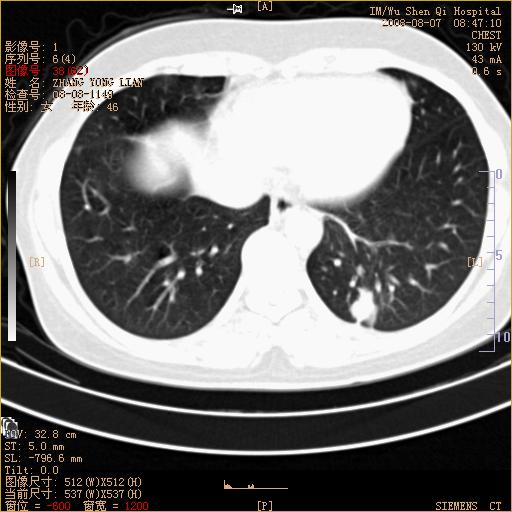

标题: CT15050:女,46岁,咳嗽胸痛一月余 [打印本页]

纵隔窗没发全,左下肺近胸膜处结节。有长毛刺,纵隔淋巴结增大,不排除恶性病变。

考虑肺癌

考虑左肺下叶后基底段周围型肺癌伴纵隔淋巴结转移可能性大。

左下肺ca并纵隔及左肺门区淋巴结转移。

脾脏低密度结节转移不排除。

1)考虑左肺下叶后基底段周围型肺癌伴纵隔淋巴结转移。2)脾内低密度灶,性质待定;不排除转移瘤可能。

恶性度很高的肺癌.